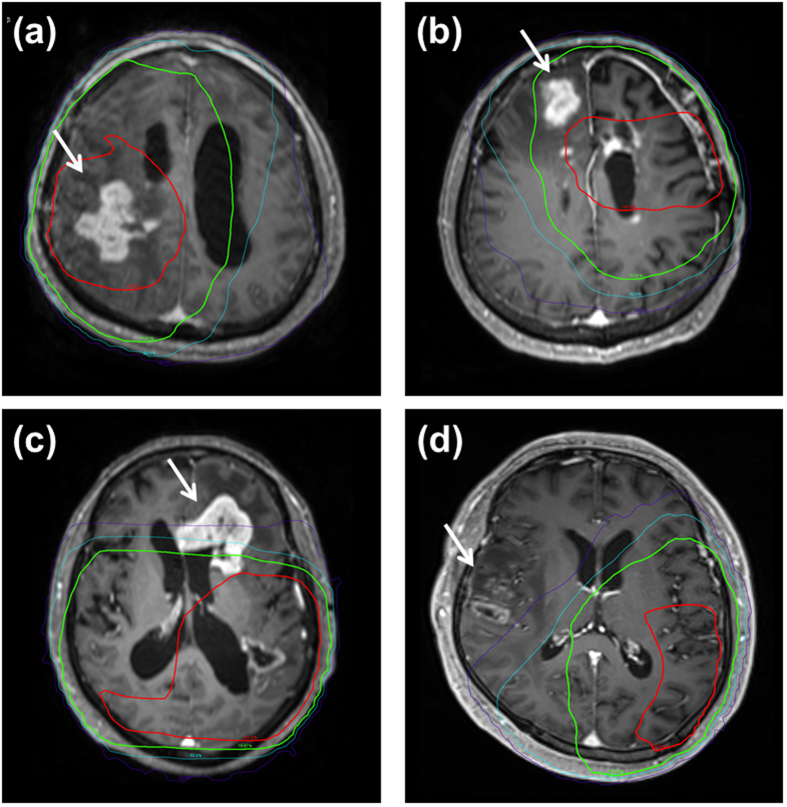

To determine the location of treatment failures, simulation computed tomography (CT) images containing isodose volumes from radiotherapy planning were co-registered with the MRI that detected treatment failure using MIM software version 6.0.6 (MIM Software Inc., Cleveland, OH)21. Disease progression was categorized as followings according to location of T1 Gd-enhancing recurrent tumor: infield GTV (within the 60 Gy volume), infield CTV (outside the 60 Gy volume but within the 46 Gy volume), marginal failure (within 2 cm from the 46 Gy volume), outfield failure (all outside the CTV), and cerebrospinal fluid (CSF) seeding. Fig. 1 illustrates examples with isodose curves from the radiation treatment plan overlaid onto the MRI at the time of failure.

Examples of (a) infield GTV, (b) infield CTV, (c) marginal, and (d) outfield failures. Red and green lines represent isodose lines of 60-Gy and 46-Gy irradiation, respectively. Sky blue line represent an isodose line of 30-Gy and purple line represent an isodose line of 12 Gy.